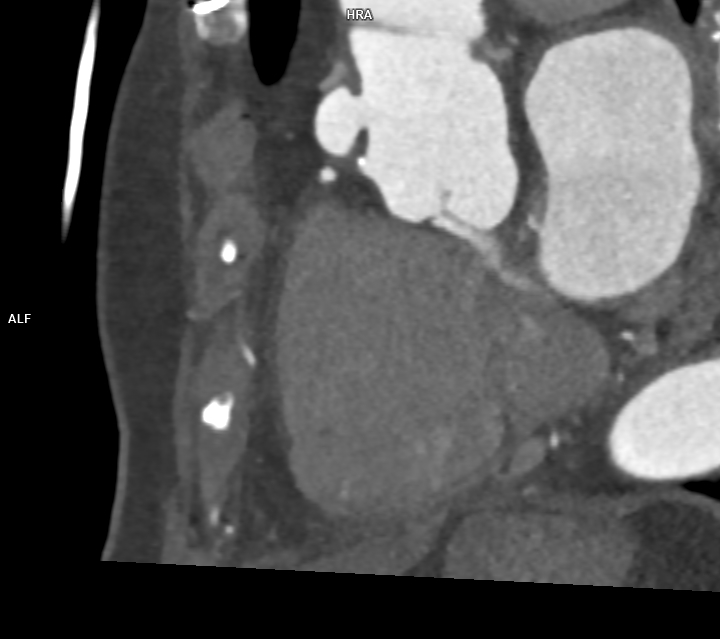

Figura 1: Reconstrucţie în planul aortei ascendente cu evidenţierea anevrismului format la inserţia inferioară a protezei de aortă ascendentă

Pacient cunoscut cu proteză de aorta ascendentă și proteză endoaortică pentru dilatație anevrismală a aortei ascendente și descendente toracice, efectuează examinare angioCT pentru control postoperator. Se evidențiază câte o dezvoltare anevrismală la inserțiile inferioară și superioară ale protezei de aortă ascendentă și proteză metalică endoaortică de aorta descendentă în poziție normală. Incidental se evidențiază un fald de disecție în segmentul proximal al arterei carotide comune stâng cu ambele lumene circulante.